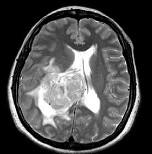

问题 女,45岁,右眼视力下降8个月,右颜面麻木半个月,时有头昏,味觉减退,请根据所提供图像,选择最可能的诊断()

选项 A.(右侧脑室)脑膜瘤(合体细胞型) B.(右侧脑室)室管膜瘤 C.(右侧脑室)脉络膜乳头状瘤 D.(右侧脑室)胶质瘤 E.(右侧脑室)转移瘤

答案 A